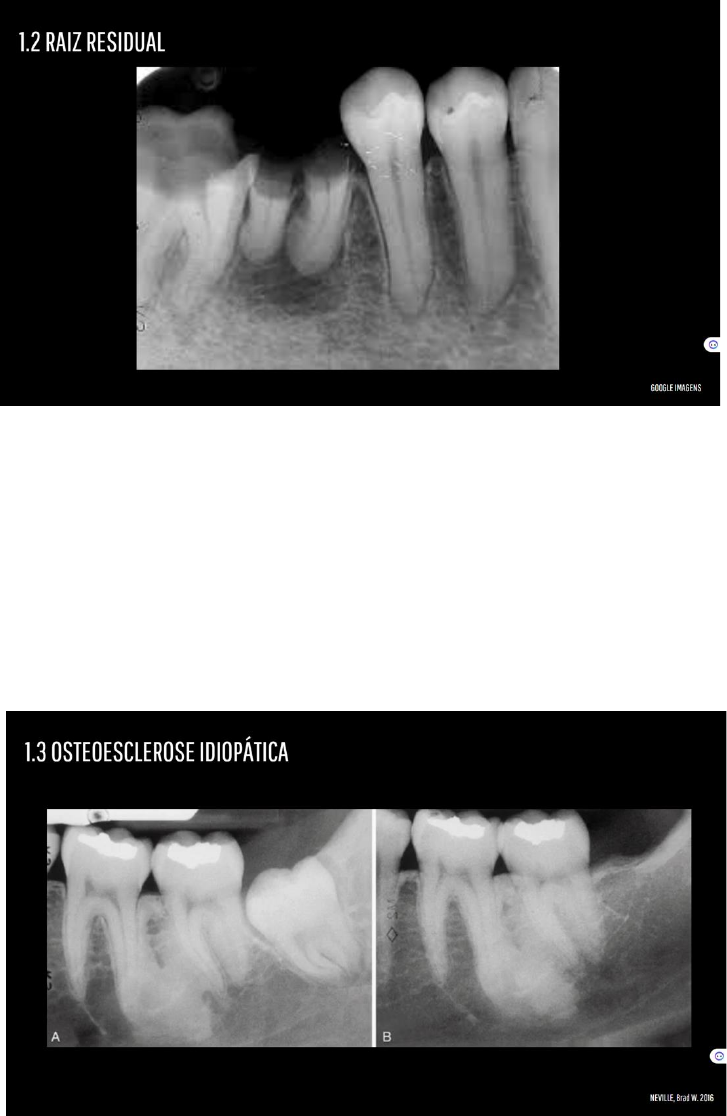

Grátis: Lesões Radiopacas - Material Claro e Objetivo em PDF para Estudo Rápido

ESTUDONTO: Lesões associadas ao osso - parte 1